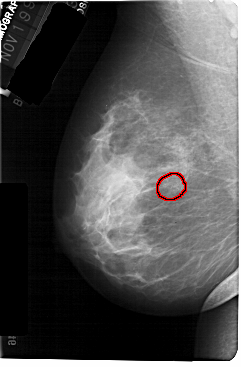

A_1301_1.LEFT_CC

LEFT_CC LINES 5491 PIXELS_PER_LINE 3511 BITS_PER_PIXEL 12 RESOLUTION 43.5 OVERLAY

FILE: A_1301_1.LEFT_CC.OVERLAY

TOTAL_ABNORMALITIES 1

ABNORMALITY 1

LESION_TYPE CALCIFICATION TYPE PLEOMORPHIC DISTRIBUTION CLUSTERED

ASSESSMENT 4

SUBTLETY 2

PATHOLOGY BENIGN

TOTAL_OUTLINES 1

BOUNDARY